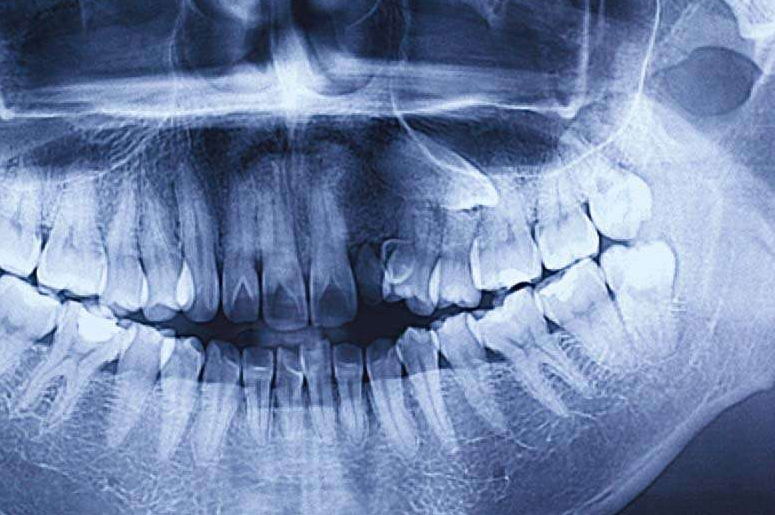

图1 恒牙牙胚发育曲断

拍X线片,对应的恒牙牙根发育超过2/3提示缺隙保持结束。

图3 多生牙阻生牙曲断

图5 埋伏牙曲断

乳牙Ⅲ、Ⅳ、Ⅴ牙冠的龋坏情况;曲断上看乳牙Ⅲ、Ⅳ、Ⅴ牙根吸收状况,若龋坏不严重可以治愈,或是牙根没有严重地吸收。